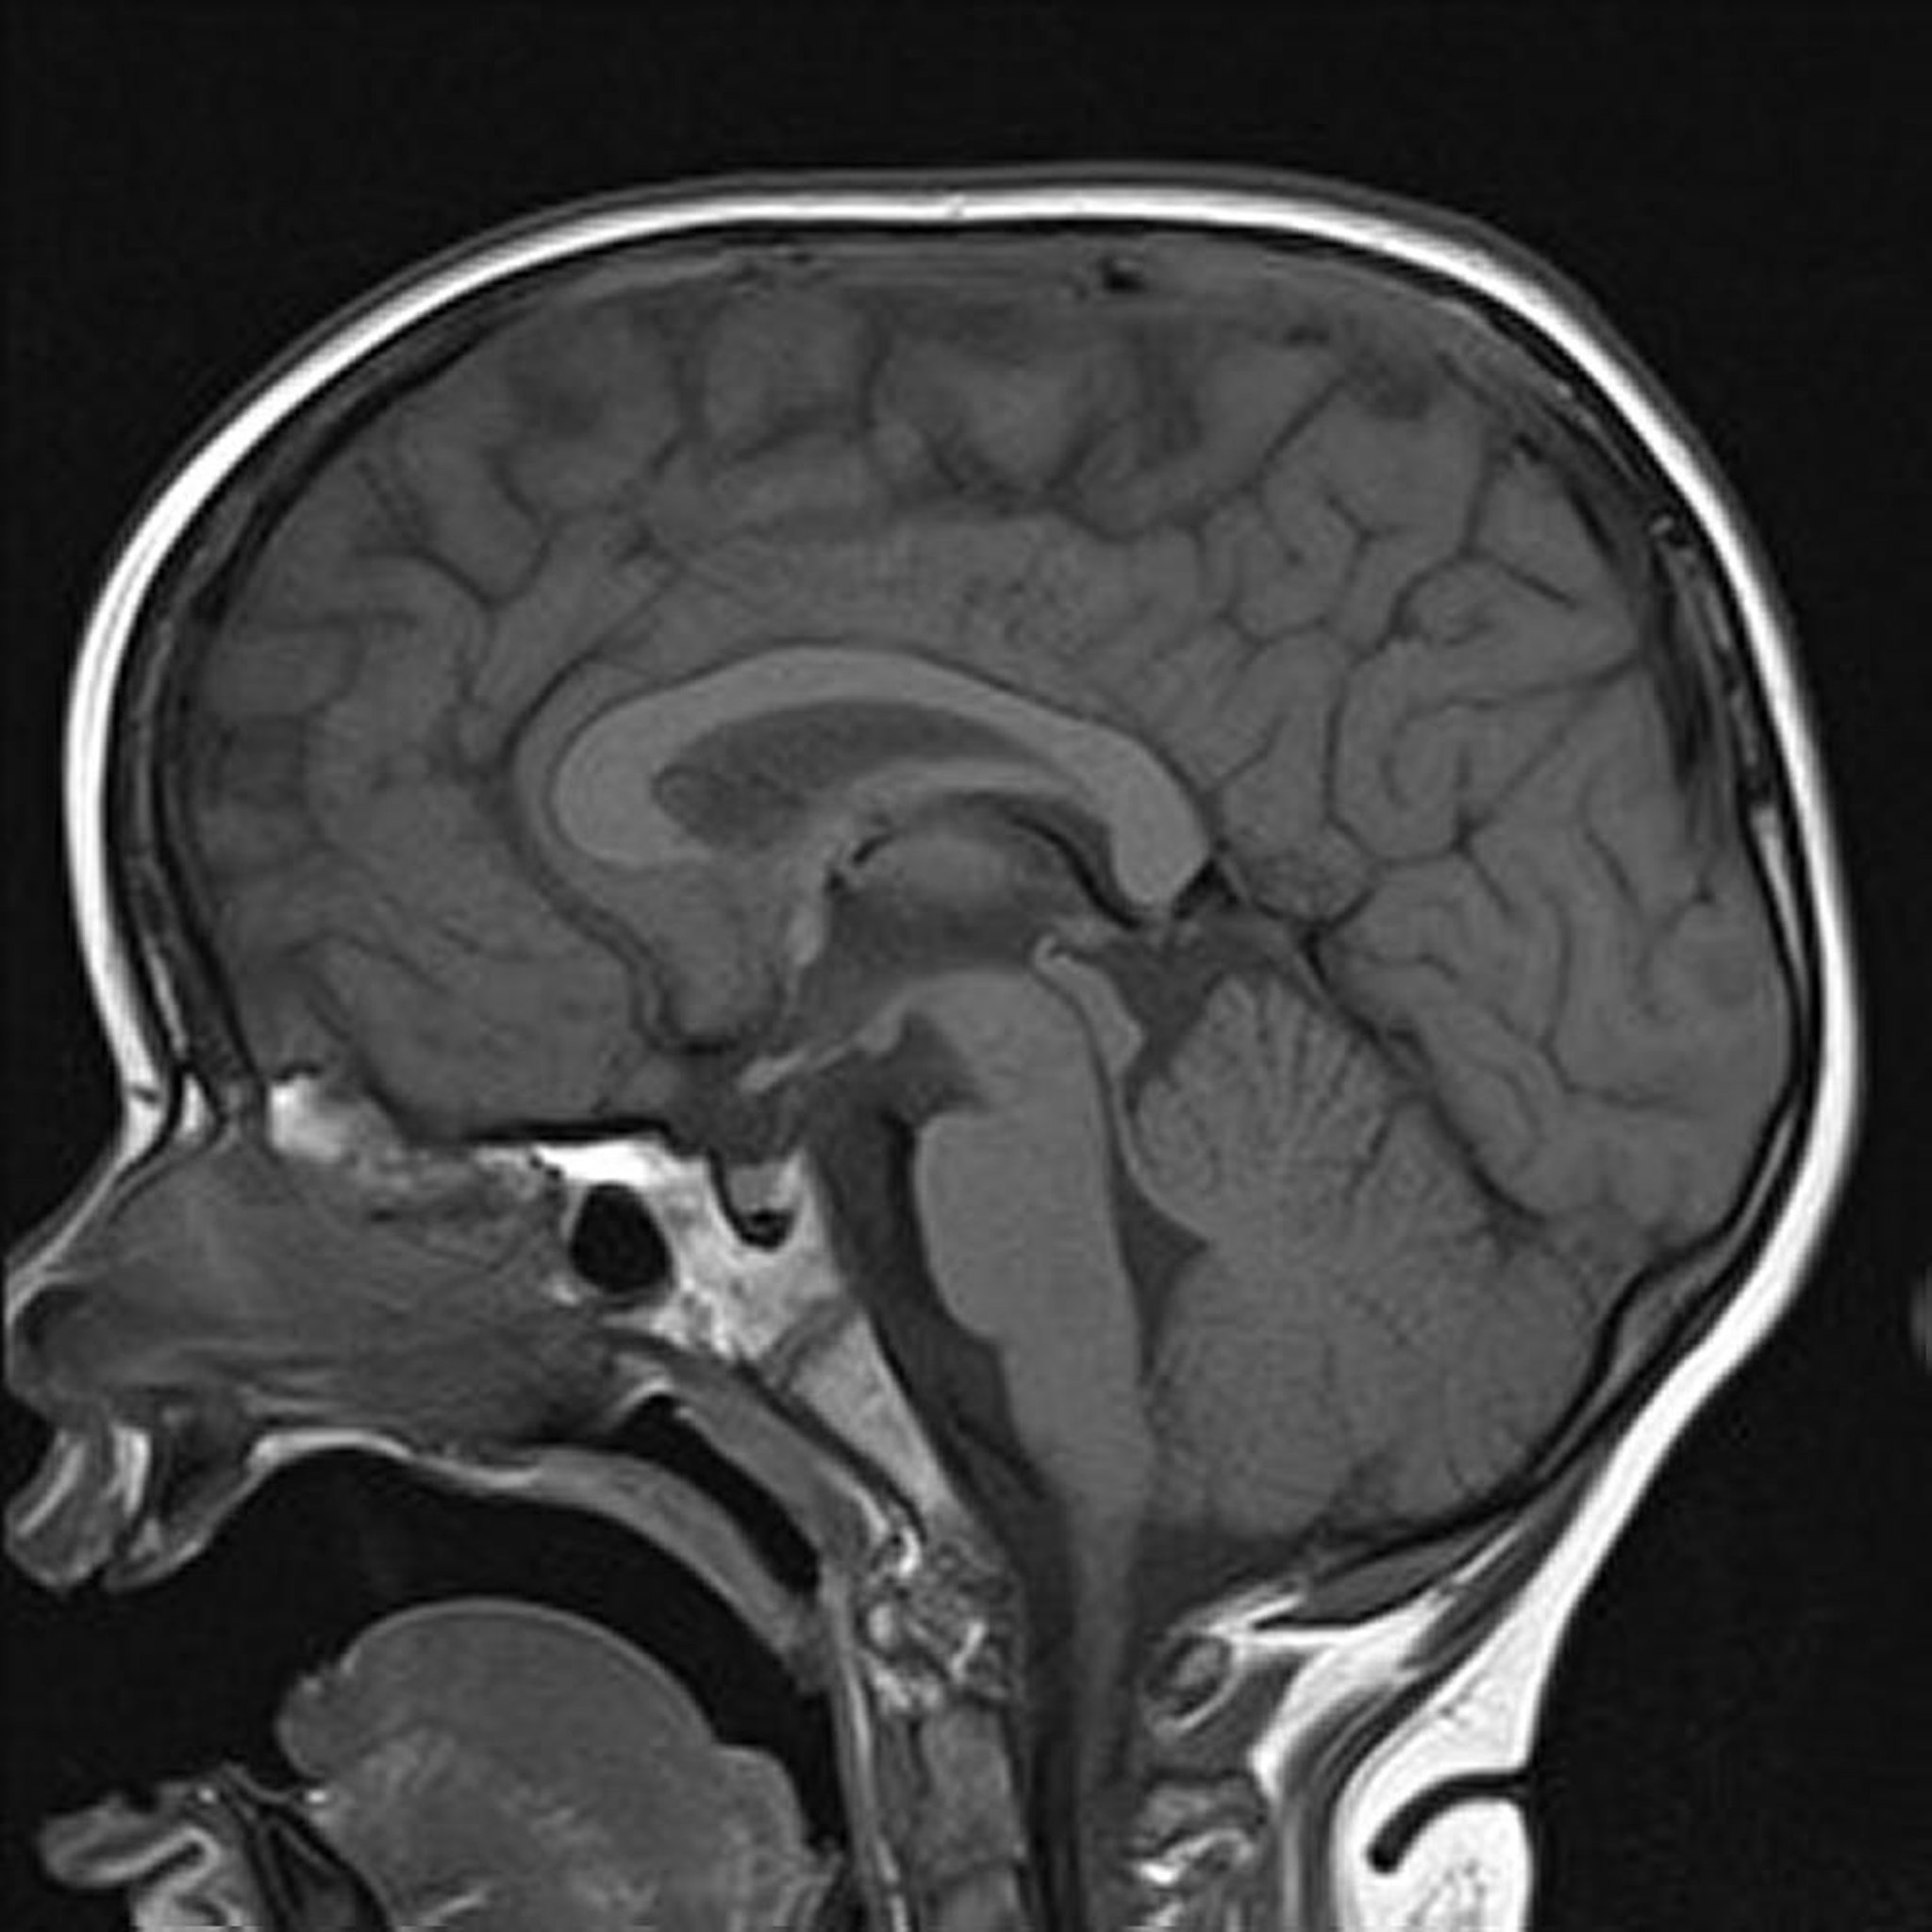

MRI theo trọng số T1

Hình ảnh não theo trọng số T1 đứng dọc cho thấy cấu trúc đường giữa bình thường.

Hình ảnh do bác sĩ Hakan Ilaslan cung cấp.